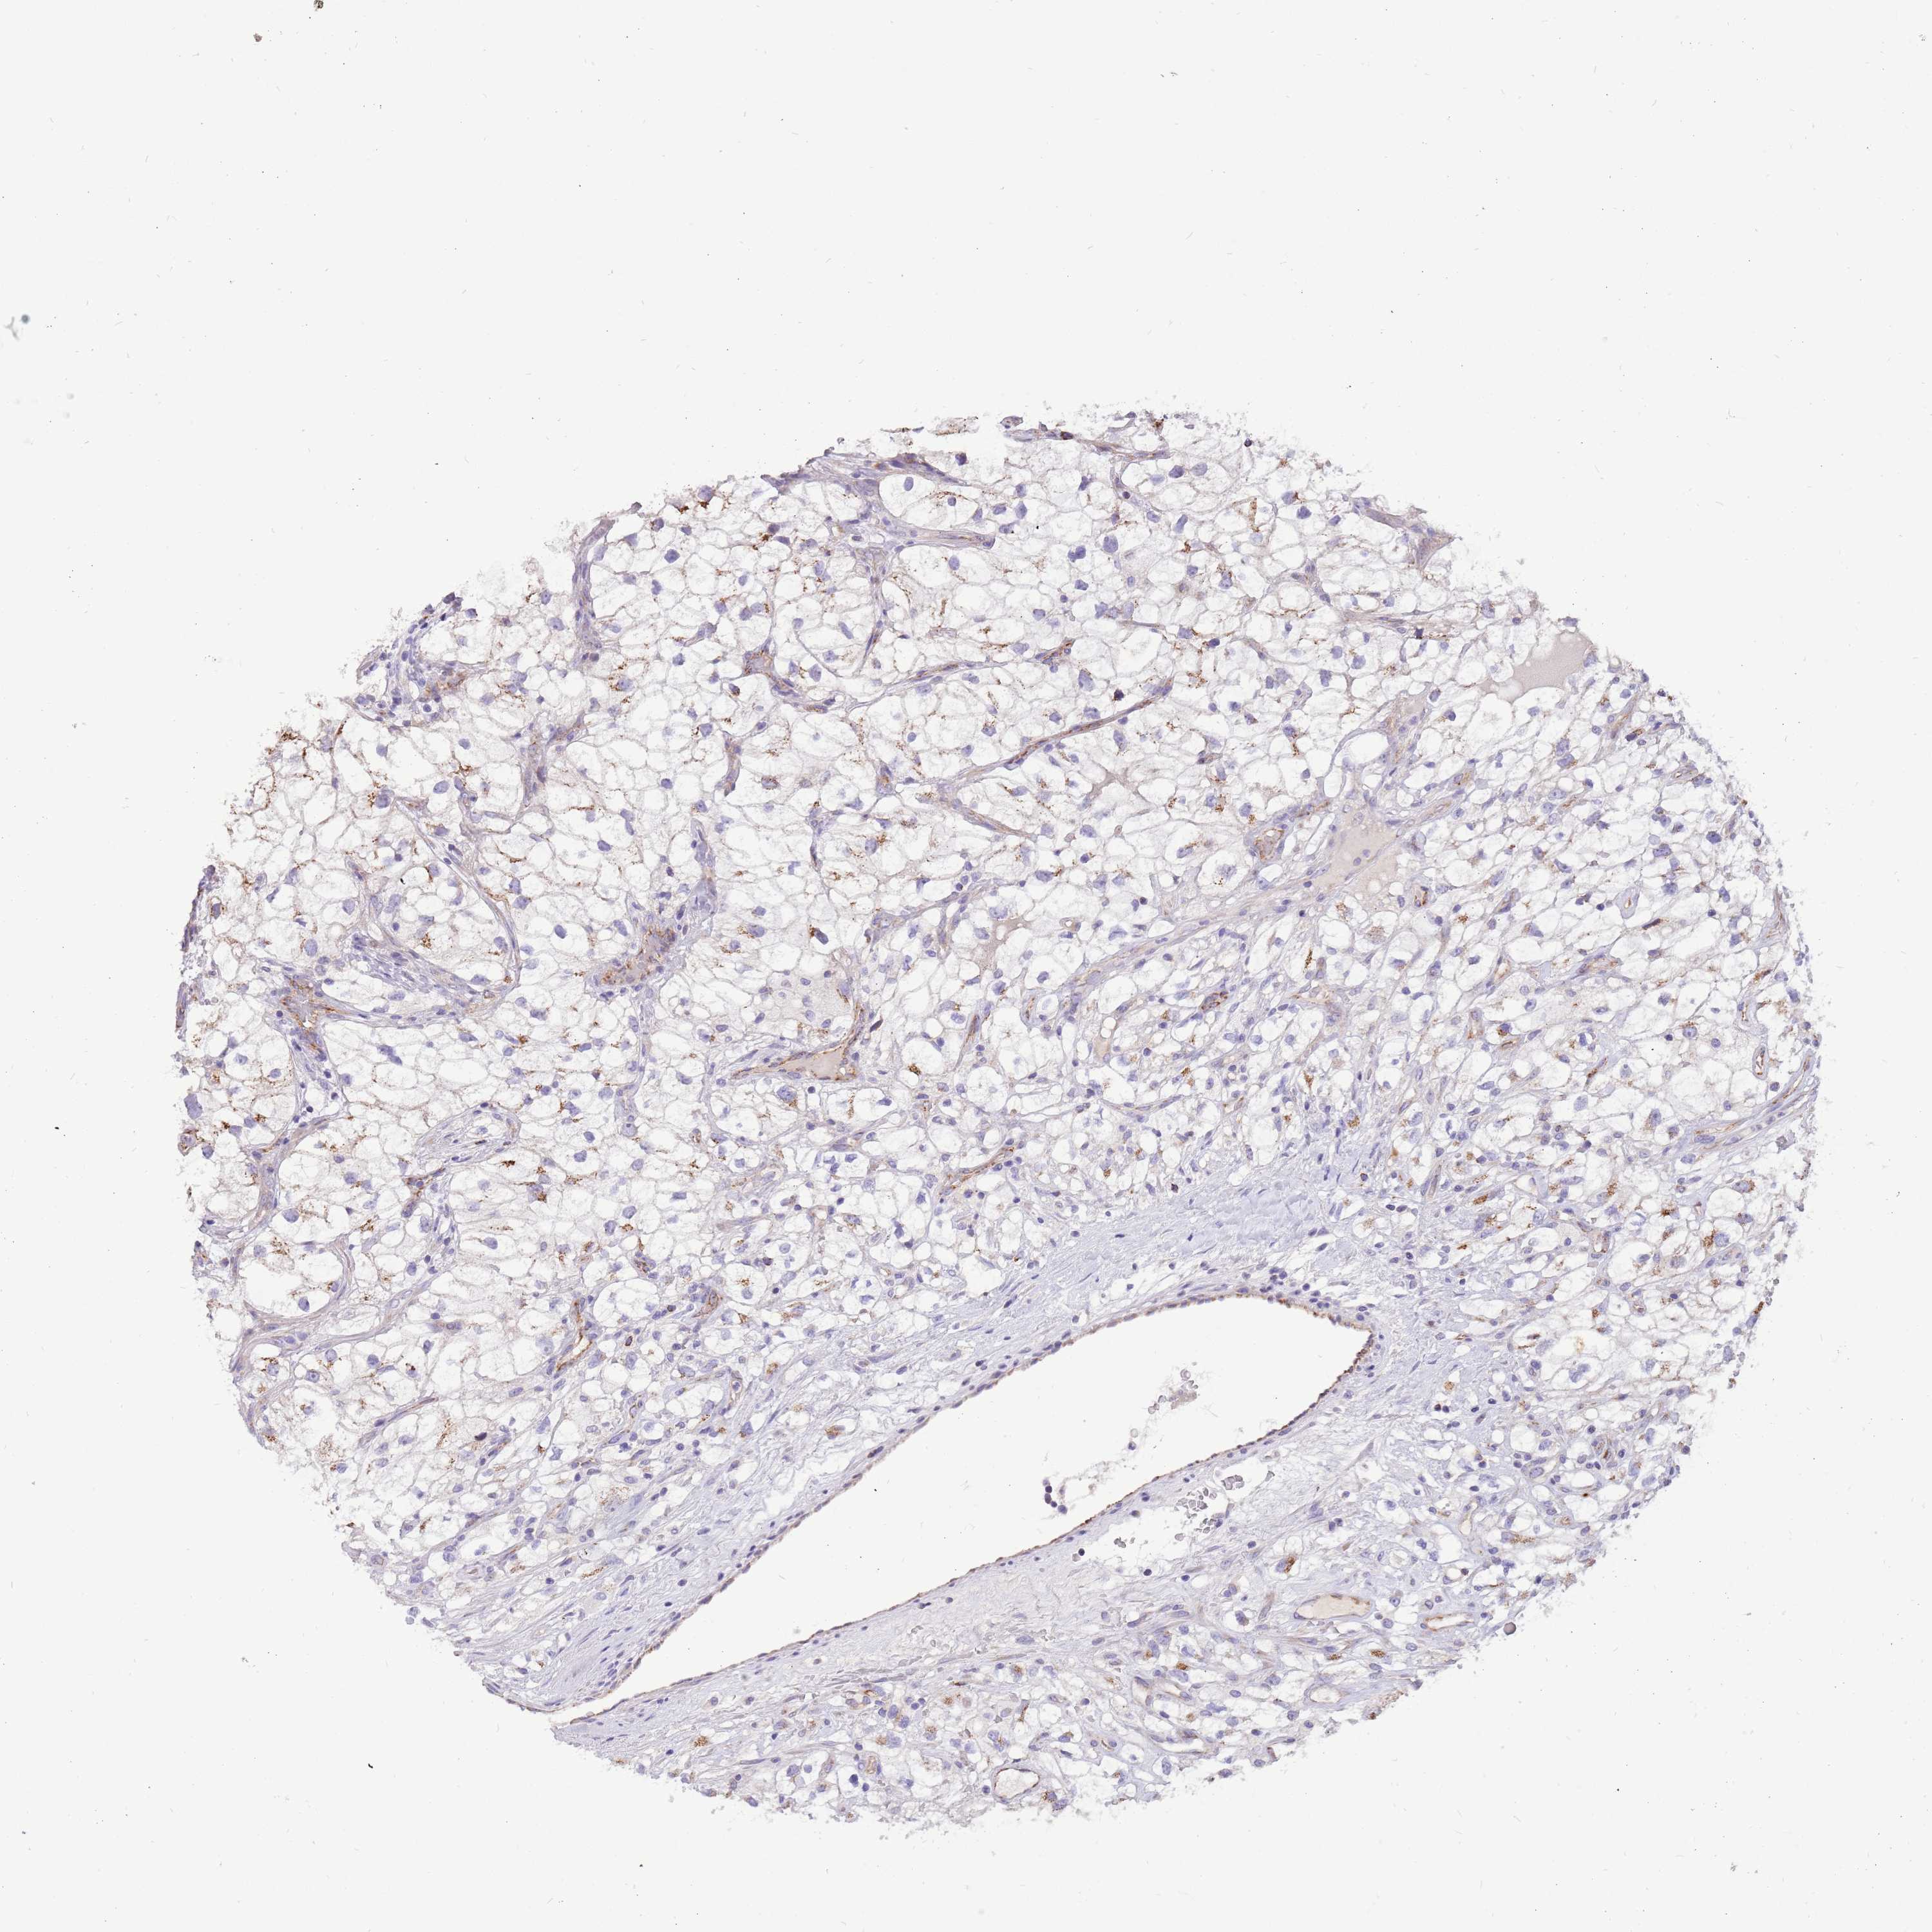

KIDNEY RENAL PAPILLARY CELL CARCINOMA (TCGA) - Interactive survival scatter ploti

The Survival Scatter plot shows the clinical status (i.e. dead or alive) for all individuals in the patient cohort, based on the same data that underlies the corresponding Kaplan-Meier plots. Patients that are alive at last time for follow-up are shown in blue and patients who have died during the study are shown in red.

The x-axis shows the expression levels (FPKM) of the investigated gene in the tumor tissue at the time of diagnosis. The y-axis shows the follow-up time after diagnosis (years). Both axes are complimented with kernel density curves demonstrating the data density over the axes. The top density plot shows the expression levels (FPKM) distribution among dead (red) and alive patients (blue). The right density plot shows the data density of the survived years of dead patients with high and low expression levels respectively, stratified using the cutoff indicated by the vertical dashed line through the Survival Scatter plot. This cutoff is automatically defined based on the FPKM cutoff that minimizes the p-score. The cutoff can be changed by dragging the vertical line or by entering a cutoff value in the square labeled "Current cut-off".

Under the Survival Scatter plot the p-score landscape (black curve; left axis) is shown together with dead median separation (red curve; right axis). Dead median separation is the difference in median mRNA expression between patients who have died with high and low expression, respectively. It is calculated as follows: median FPKM expression of dead patients with high expression - median FPKM expression of dead patients with low expression. This is intended to aid the user in visually exploring custom cutoffs and the associated p-scores and dead median separation.

Individual patient data is displayed and can be filtered by clicking on one or more of the category buttons on the top of the page. Categories describing expression level and patient information include: high, low, alive, dead, female, male and tumor stages. The scale of the x-axis can be toggled between linear and log-scale by clicking on the "x log" button. Mouse-over function shows TCGA ID, patient information and mRNA expression (FPKM) for each patient.

& Survival analysisi